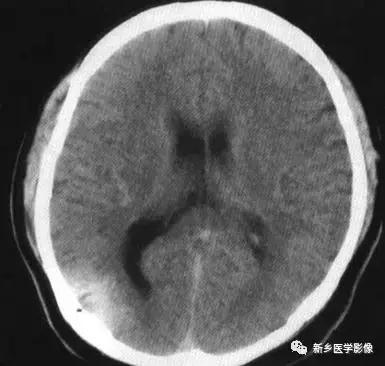

(1)前脑无裂畸形: (holoprosencephaly)是指一系列位于中线程度不同的畸形,累及大脑、面部、脑于和小脑.前脑未能够分开,呈不全性或完全性,端脑和间脑无法区分。根据脑及面部畸形程度将其分为无叶型、半叶型和单叶型。

无叶型前脑无裂畸形最严重.端脑半球间没有裂隙,呈马蹄形或新月形扩大的单脑室跨越中线,与背侧囊交通。丘脑互相融合,面部畸形从两眼距离过近到独眼畸形.往往死于胎儿或新生儿期。

半叶型前脑无裂畸形在前脑可见部分裂隙. 形成不同发育程度的大脑纵裂及大脑镰。两侧大脑半球在前部未完全分开,但枕叶和 双侧侧脑室体部分离,丘脑分开不完全。三脑室和海马发育不全,胼胝体仅可见到压部,而其他部分缺如.额叶和基底节前部分辨不清。临床表现有两眼距离过近.及唇裂、腭裂等面部畸形,侧脑室呈单一性.且明显扩大。

单叶型前脑无裂畸形与正常发育脑仅有些很小的区别.如透明隔缺如或双侧额叶不完全分开。